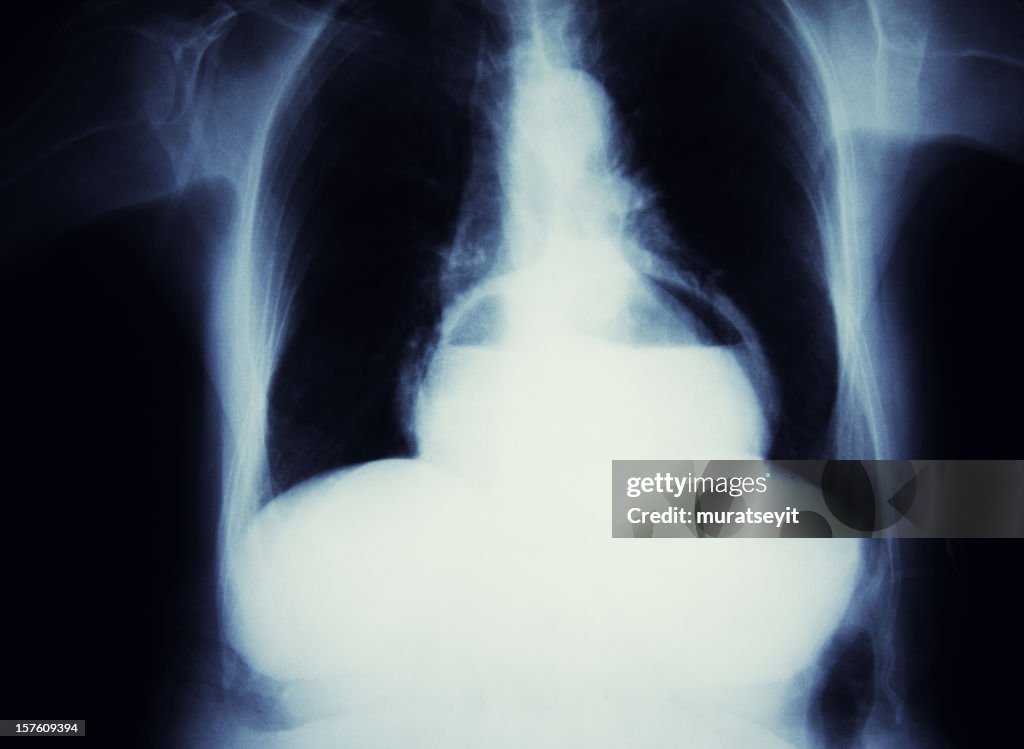

Hernia of the stomach - Stockfoto

Getty ImagesHernia Of The Stomach, Stockfoto Download premium, authentieke Hernia of the stomach stockfoto's van Getty Images. Verken vergelijkbare stockfoto's met hoge resolutie in onze uitgebreide visuele catalogus.Product #:157609394

Download premium, authentieke Hernia of the stomach stockfoto's van Getty Images. Verken vergelijkbare stockfoto's met hoge resolutie in onze uitgebreide visuele catalogus.Product #:157609394

Download premium, authentieke Hernia of the stomach stockfoto's van Getty Images. Verken vergelijkbare stockfoto's met hoge resolutie in onze uitgebreide visuele catalogus.Product #:157609394

Download premium, authentieke Hernia of the stomach stockfoto's van Getty Images. Verken vergelijkbare stockfoto's met hoge resolutie in onze uitgebreide visuele catalogus.Product #:157609394€335€50